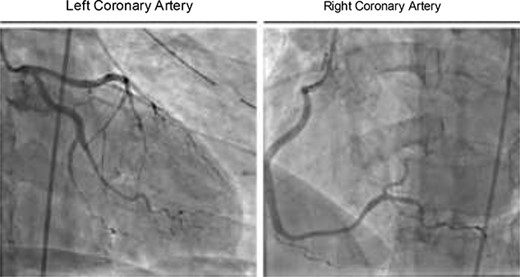

In the ICU, the patient was tachycardic and began to complain of chest pain. At this time, a 12-lead electrocardiogram (ECG) demonstrated diffuse S and T wave segment elevations in leads I, V2–6 (Fig. 2). Based on these observations and a significant elevation in serum troponin (0.12 ng/L, normal range 0.0–0.4 ng/L), the patient was oxygenated, given aspirin and nitroglycerine, as well as morphine for pain. Cardiology was consulted and performed a bedside transthoracic echocardiogram but was unable to completely visualize due to the extensive subcutaneous emphysema. Urgent coronary angiography demonstrated occlusion of the apical left anterior descending artery and stenosis of the second obtuse marginal artery with angiographic appearance (Fig. 3), consistent with coronary artery dissections.

Coronary angiography showing occlusion of the apical left anterior descending artery and stenosis of the second obtuse marginal artery.